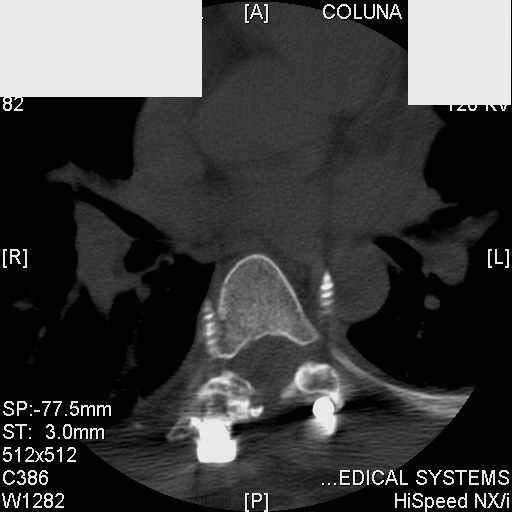

Interesting case. Findings on CT: all four pedicle screws have been placed improperly inthat they miss the vertebral bodies. In addition, the screws on the left side are impingingon the decending thoracic aorta. What I do NOT know is the nature of the original injury, orwhether or not that injury has resolved. I would recommend removal of the hardware. I don'tthink it's a good idea to leave those screws where they are. If the original fracture ishealed, nothing else needs to be done.

dear Mark, all the details are not yet available but the patient is coming to see us foradvice. We probably will see him in the early new year. i thought that the 4th picture showedthe screw to enter the aorta? He is a victim of a motor vehicle crash and thoracic vertebralfracture which appears healed. He was posteriorly decompressed and this device inserted. asyou say there isno evidenece that any of the fixation enters the bodies via the pediclesistead they have passed thru and their end are no where near where they ought to be. If I amcorrect (I would prefer not to be) the aortic intima has been breached by the screw. When thetime comes to take the screw out I thought we should have control of the aorta.What do you think?

Tom: I strongly doubt that the aorta is involved. When these screws are put in, they firstput in a probe, then a tap, then the screw. If the aorta was punctured, they would have knownat the time. You might call the original surgeon (if in fact he is a real doctor) and get hisfeedback. The additional morbidity of a prophylactic thoracotomy would be a higher pricethan I would be willing to subject my patient to. Besides, it would be exceptionallydifficult to control the aorta at this point, especially if you tried to specifically getenough control to be able to put sutures in the back wall. Of course, difficulty of doingsomething isn't necessary a reason not to do it if you think it is necessary. I just think itis highly unlikely that the aorta is injured. I showed the case to both a thoracic surgeon anda neurosurgeon. The thoracic surgeon suggested getting an arteriogram to see if the aorta isinvolved. The neurosurgeon agreed that the hardware should be removed.

Mark Thank you. He is scheduled for a angio prior to transfer here. I keep going back to lookat that fourth image and although it is tough to believe the wall of the aorta seems toencompass the distal 1/2 of the screw. I have come to anticipate mal postion of screws thathave been inserted in hospitals that perhaps may not have the highest quality of equipment,including the human and radiological components. That having been said this case seems tosurpass the usual... one screw out of place or screwed into a disc etc. BTW I am notsuggesting that the screw was placed directly into the aorta but that moviment, pulse actionetc may have caused it to transgress the normal anatomical bounds without evident hemorrhage.

Подошли ангиограммы... Наслаждайтесь...

травматический обратный дивертикул аорты!

На этом уровне аорта интимно седенина с columna vertebralis? а иначе, если бы она была подвижна, шуруп не вошел бы в нее. Учитывая интимную связь аорты и позвонка - удаление конструкции может привести к кровотечению по ходу канала от шурупа, что можно предотвратить тампонированием аллотрансплантанта.Посудите сами - если кровотечение в средостение должно произойти оно бы уже произошло. Удачи!